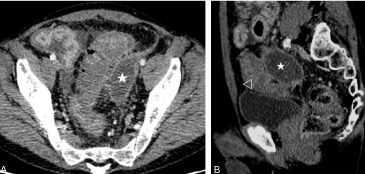

- L’abcès périsigmoïdien (figure 6.3) correspond à une collection de contenu liquidien ou hydroaérique, à parois rehaussées, à proximité du côlon diverticulaire.

Fig. 6.3 Diverticulite compliquée d’un abcès (Hinchey 2).

Scanner au temps portal après injection de produit de contraste iodé. Collection extradigestive pelvienne de contenu hydroaérique (∗) au contact d’un sigmoïde diverticulaire (tête de flèche), en rapport avec une diverticulite compliquée d’abcès périsigmoïdien.

Source : CERF, CNEBMN, 2022.